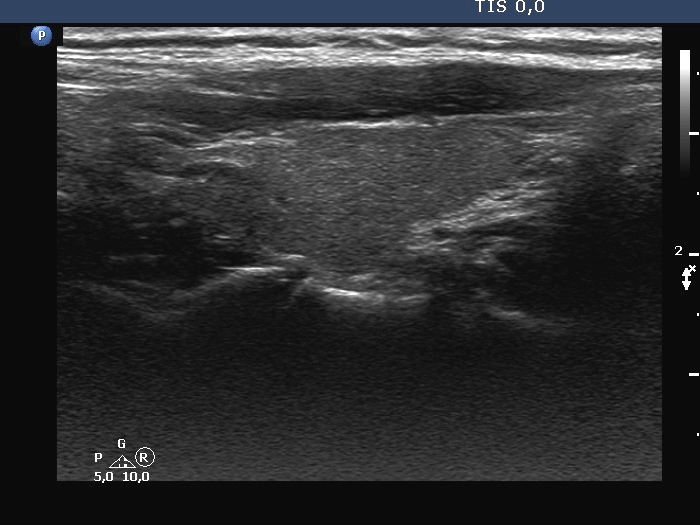

The borders of the nodule - case 2169 (ultrasonographic picture 2)

Right lobe, longitudinal scan

Right lobe, longitudinal scan. There is a bit more hypoechoic lesion in the upper pole.